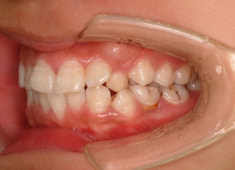

治療前